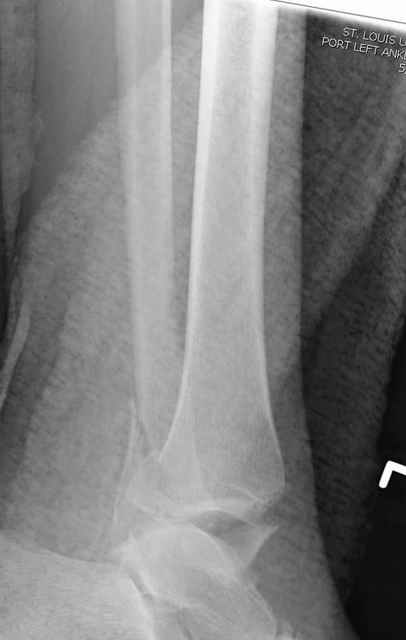

Pilon fracture:

ET> ЕЧ При подобных переломах фиксация малоберцовой кости обеспечивает

ET> низведение латерального тибиального фрагмента - появляется ориентир для

-Появляется ориентир и остов, на чем можно строить восстановление, почему сперва малоберцовую, впервые обьяснили и описали (Pylon type and Ankle fractures) в середине 50х Rienau и Gay.

Восстановливая длину и ротацию малоберцовой кости, затем относительно легче произвести реставрацию остальных элементов перелома дистального эпиметафиза болшеберцовой кости.

где исследования на трупах показали, что малоберцовая кость участвует в стабильности голеностопного сустава, поддерживая наклон тарана (talar tilt) за счет связок. После ознакомления работой Ramsey в ортопедию ввели термин "при переломах голеностопного сустава смещенная

таранная кость следует за малоберцовой костью" т.е. связка не рвется, а тянет таран за собой, поэтому восстановление малоберцовой кости в

первую очередь, затем остальных элементов - стал классическим при лечении данной патолгии. Латеральная колонна (столб), дистальный

конец малоберцевой кости, к нему прикрепляется латеральный суставной фрагмент дистального эпиметафиза большеберцовой кости (как на снимке)

и таранная кость, которые при репозиции малоберцовой кости репонируются автоматически.